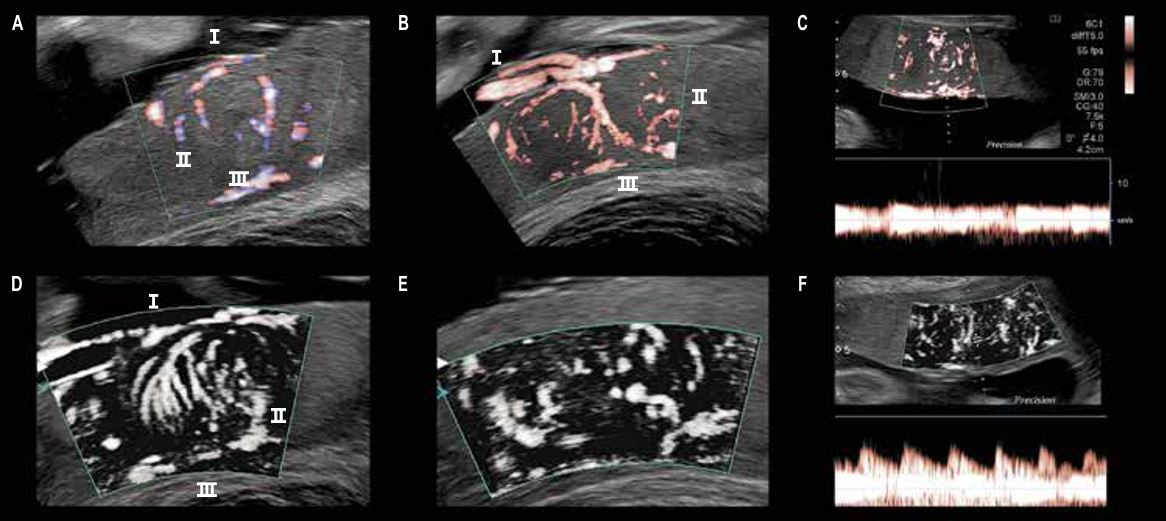

Візуалізація фетоплацентарної васкуляризації за допомогою SMI (мал. 1)

Дослідження за допомогою класичного енергетичного допплера дозволяють ідентифікувати дрібні судини базальної пластини плаценти (материнська частина плаценти), а дрібні судини хоріонічної пластинки (плодова частина) рідко виявляються за пупковими артеріями; іноді видно головний ствол ворсинчастої мережі.

Тим не менш, побачити ворсинчасті мікросудини неможливо: діаметр таких судин зазвичай трохи більше 500 –1000 мікронів на початку другого триместру вагітності, а, ближче до пологів, лише кілька міліметрів, але за допомогою технології SMI можна легко побачити ворсинчасту судинну мережу, навіть якщо діаметр судин настільки малий.

Мал. 1. Нормальна васкуляризація плаценти: A – традиційний доплер; B, D, E – технологія SMI; C, F - імпульсний доплер у поєднанні з методом SMI

І. Хоріальна пластина = плідна частина плаценти

Артерії пуповини поділяються на кілька гілок на рівні хоріальної пластини плаценти. Ці гілки дають початок артеріям, що проникають у стовбурові ворсини (мал. 1B та 1D).

ІІ. Міжворсинчастий простір

містить хоріонічні ворсини, через які проходять міжворсинчасті артерії та вени. Всі ворсини рясно кровопостачаються. Тільки технологія SMI дозволяє візуалізувати судинну мережу у середині ворсин (мал. 1D, 1E та 1F).

ІІІ. Базальна пластина = материнська частина плаценти

Плацентарні артерії виходять із спіральних артеріол (мал. 1E).